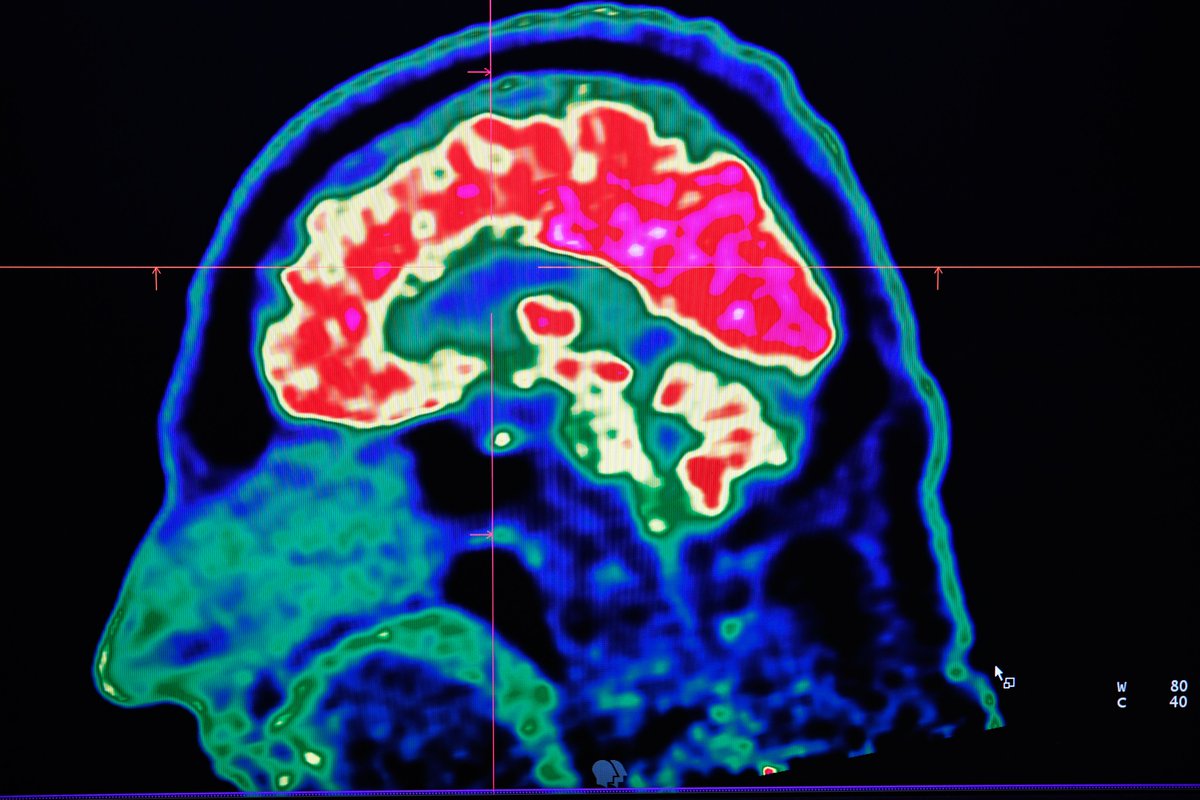

طلب الباحثون من المشاركين الـ 12 الاستلقاء في جهاز تصوير بالرنين المغناطيسي الوظيفي، وتوضيحاً، يقيس جهاز التصوير هذا نشاط الدماغ عن طريق الكشف عن التغييرات المرتبطة بتدفق الدم إلى أجزاء مختلفة منه

تعتمد هذه التقنية على حقيقة أن تدفق الدم إلى الدماغ والنشاط العصبي مرتبطان ببعضهما بعضاً بشكل مباشر، وعندما يكون جزء من الدماغ قيد الاستخدام يزداد تدفق الدم إليه أيضاً